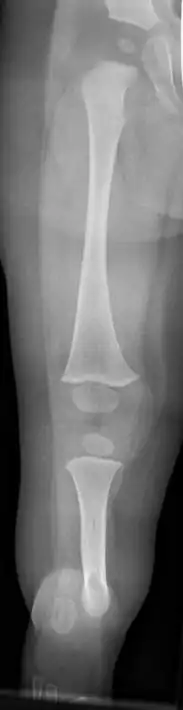

Fibula hemimelia in patient affecting right side

X-ray image of fibular hemimelia type II (fibula completely absent)